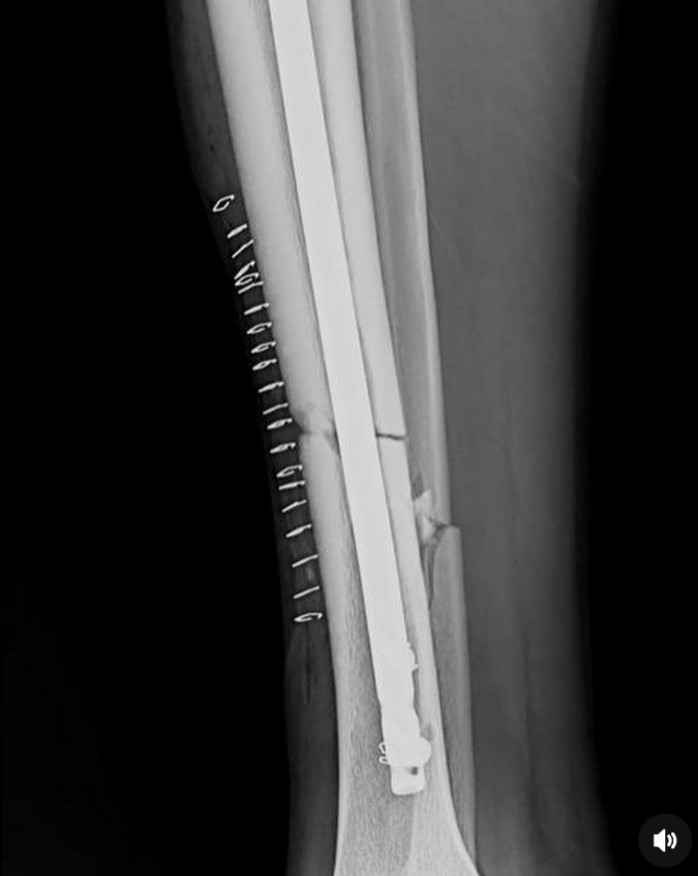

‘Igufwa ryahise ricika mo kabiri’  Dore amafoto yo mu byuma byo kwa muganga agaragaza uburyo igufwa rya Kimenyi Yves ryatandukanye ubwo yavunikaga

Ubwo Kimenyi Yves yari arimo ashimira Imana n’abantu bamubaye hafi mu bihe ari gucamo, abinyujije ku rukuta rwe rwa Instagram yasangije amafoto y’uburyo igufwa rye ryabaye ubwo yavunikaga.

Kimenyi yavunitse mu mukino As Kigali riheruka gukinamo na Musanze Fc bikarangira Musanze itsinze As Kigali igitego kimwe ku busa.